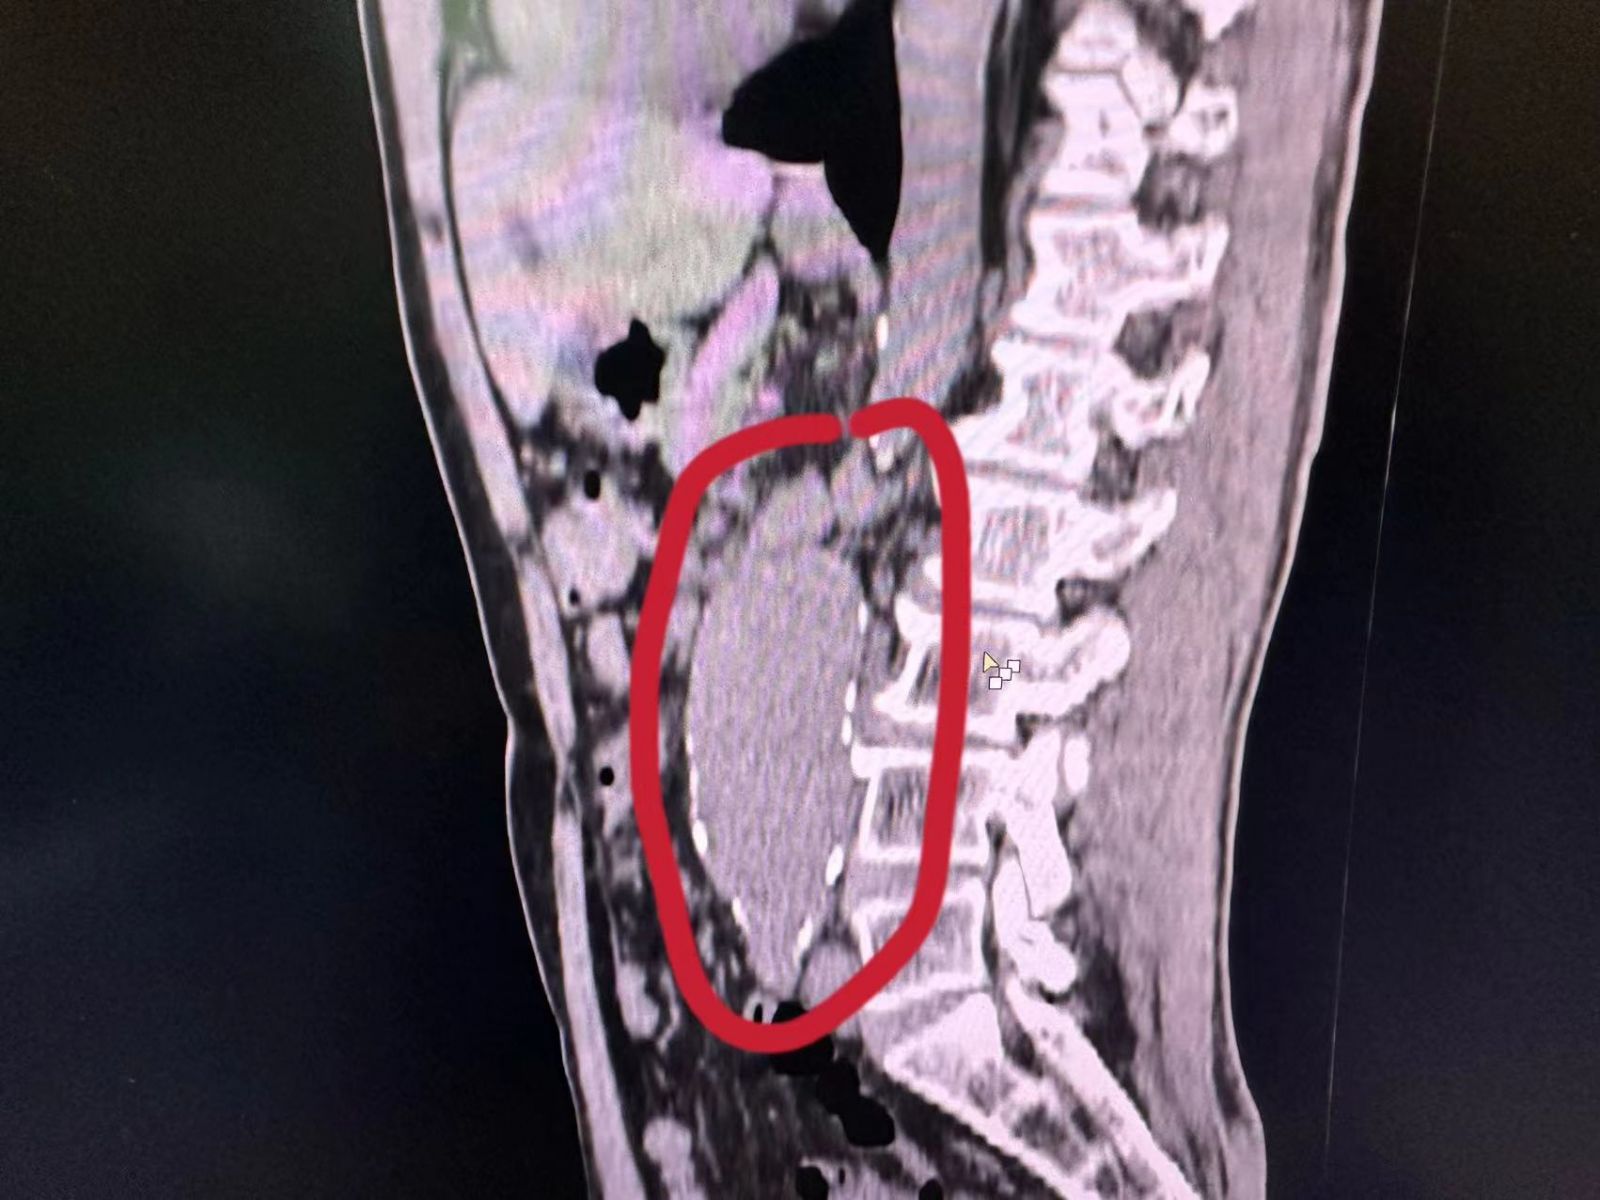

近日,一次常规门诊CT检查,在潘先生身上照出惊人一幕:腹主动脉瘤,腹主动脉壁上赫然膨出一个“定时炸弹”!这颗随时可能破裂的“炸弹”,让平静的门诊瞬间涌起紧张暗流。

腹主动脉瘤素来凶险,瘤体一旦破裂,九成患者抢救不及,生命将如风中残烛,片刻即灭。发现腹主动脉瘤必须立即转往具备血管外科手术能力的上级医院,生命通道刻不容缓。